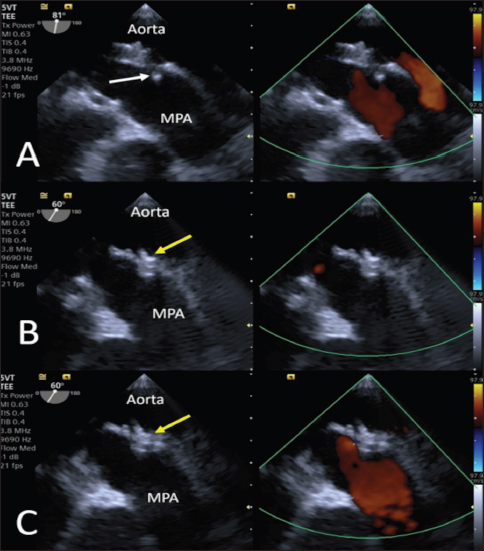

Anesthesia was induced and maintained as previously described (Bagardi et al., 2022) and perioperative intravenous amoxicillin (22 mg/kg) was administered. The dog was placed in right lateral recumbency on a fluoroscopy table (C-arm: Siemens Cios Select Siemens Healthcare), and the area over the right femoral artery was clipped and prepared for surgery. The patient was monitored with transesophageal echocardiography (TEE; Probe: 5VT, Siemens Healthcare), which allowed optimal visualization of the ductus and its measurements (MDD 1.2 mm, ampulla diameter 3.8 mm, and length 4.4 mm), which confirmed the choice of the device (Fig. 3).

Fig. 3. Intraoperative TEE showing PDA and its measurements (MDD: 1.2 mm; ampulla diameter: 3.8 mm; length: 4.4 mm) and the flow from the aorta to the pulmonary artery (MPA) on CFM Doppler (Dual-mode).